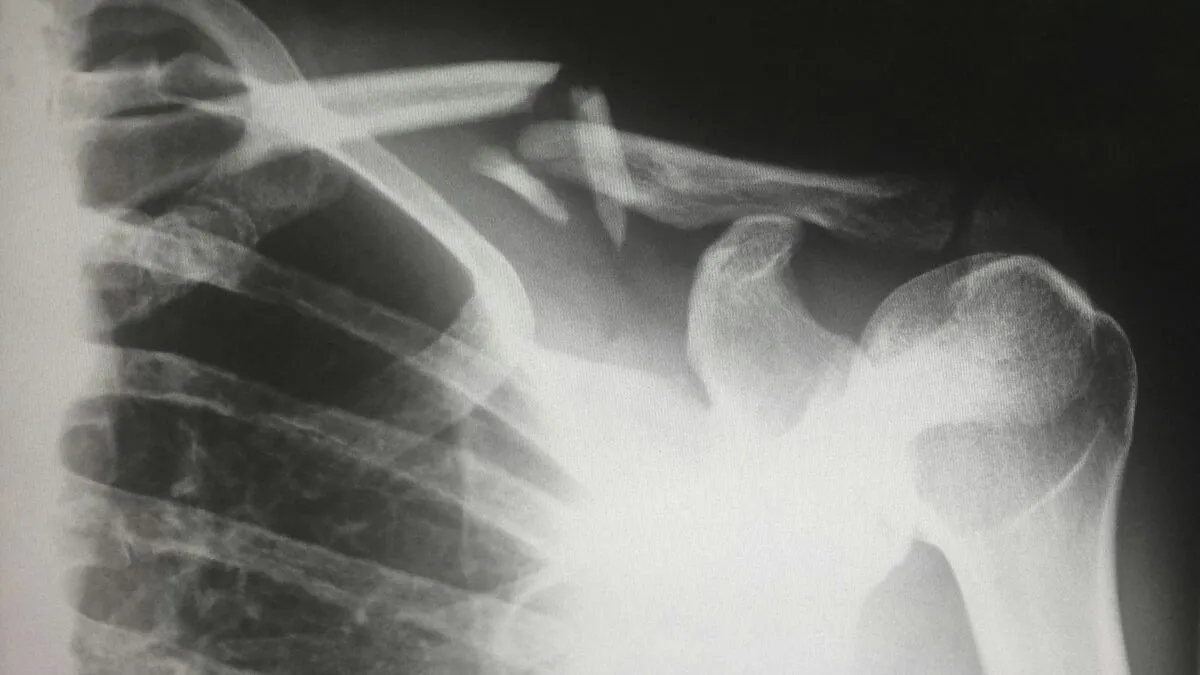

A röntgenen fedezték fel a testében lévő kést

Végül egy mellkasröntgen feltárta a jelenlegi problémájának okát, ami egy nagy késpenge volt, amely a mellkas középső részébe fúródott.

Az orvosok megállapították, hogy a kés a jobb lapockán keresztül hatolt be, és valahogy elkerült minden létfontosságú szervet. A műtét során a pengét óvatosan eltávolították, a gennyes váladékot, amely az elhalt szövet miatt keletkezett, pedig lecsapolták.